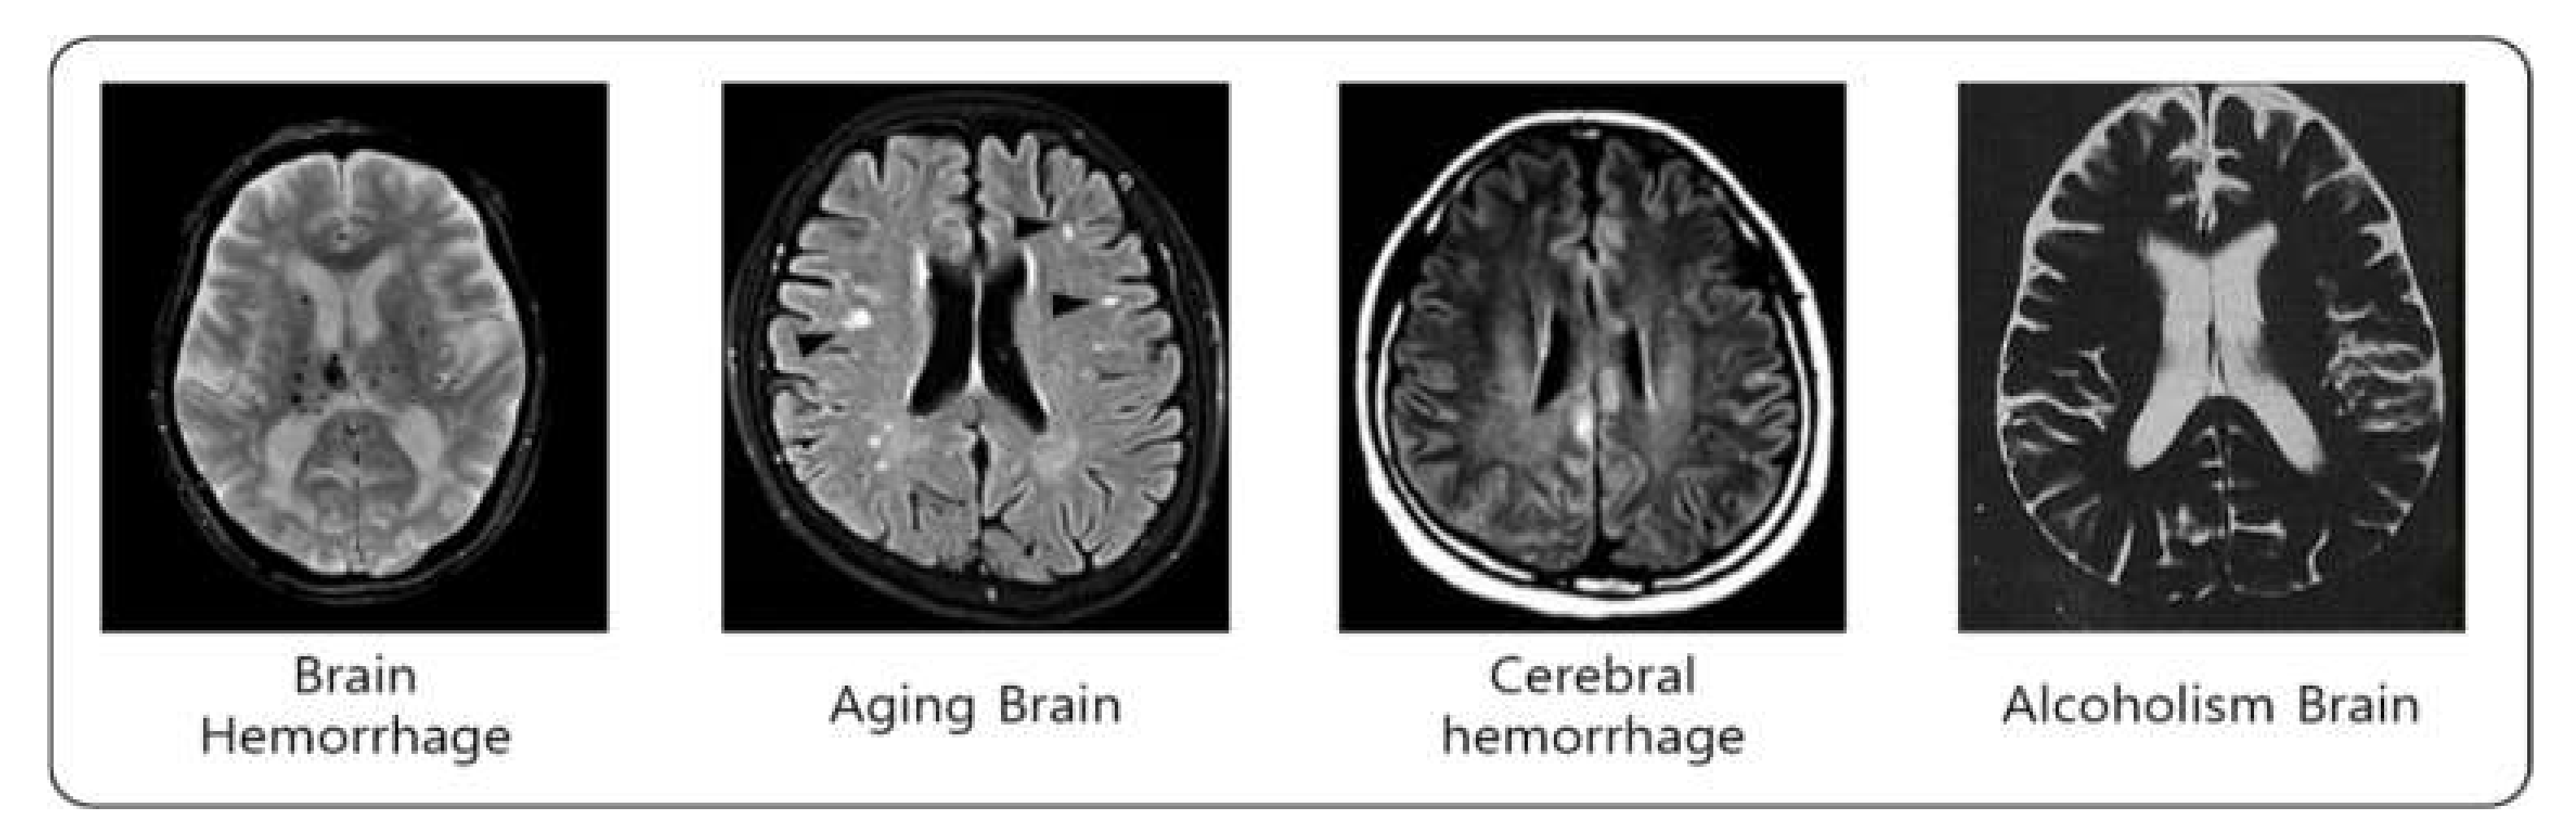

- Image style transfer is a method for transforming image style by keeping the main form of the image using two-image data in the computer vision and, additionally, applying the desired style. Through this, changes in the brain are predicted by transferring the factors affecting dementia.

- Since the background of the image was not removed in the existing method, unnecessary attributes were applied to the image style transmission. In order to solve this problem, the ‘existing method+background removal’ removes unnecessary attributes, but the performance is evaluated poorly because differentiated weights are not applied in each step. However, the proposed method has a different weight and reduces the amount of computation by removing the background in order to prevent unnecessary attribute style transmission, so the performance is evaluated well.